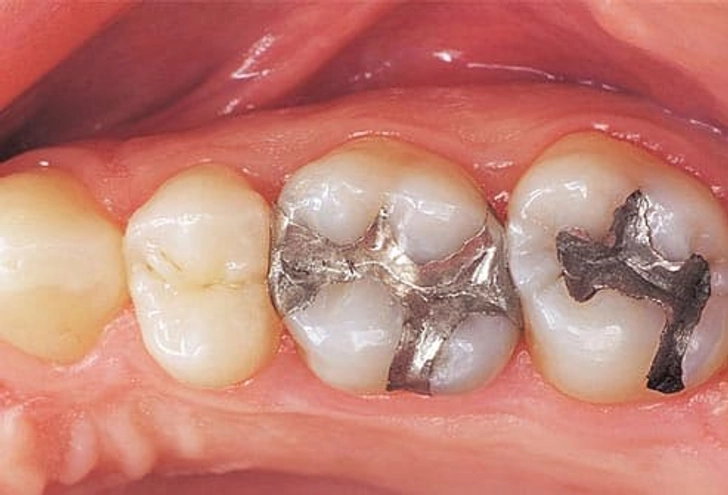

۳. پوسیدگی دندان (Cavities)

این حفره های کوچک و پوسیدگی ها در دندان خبر خوبی نیستند. زمانی ایجاد میشوند که باکتری چسبندهای به نام پلاک (Plaque) روی دندان تجمع کرده و به تدریج مینای دندان را تخریب میکند. پوسیدگی میتواند در خط لثه یا اطراف ترمیمهای قبلی هم رخ دهد.

راهکارهای درمان:

- ترمیم با کامپوزیت یا آمالگام

- روکش های دندانی pfm یا زیرکونیا

- در صورت نیاز انجام درمان ریشه

- لمینیت های تمام سرامیکی